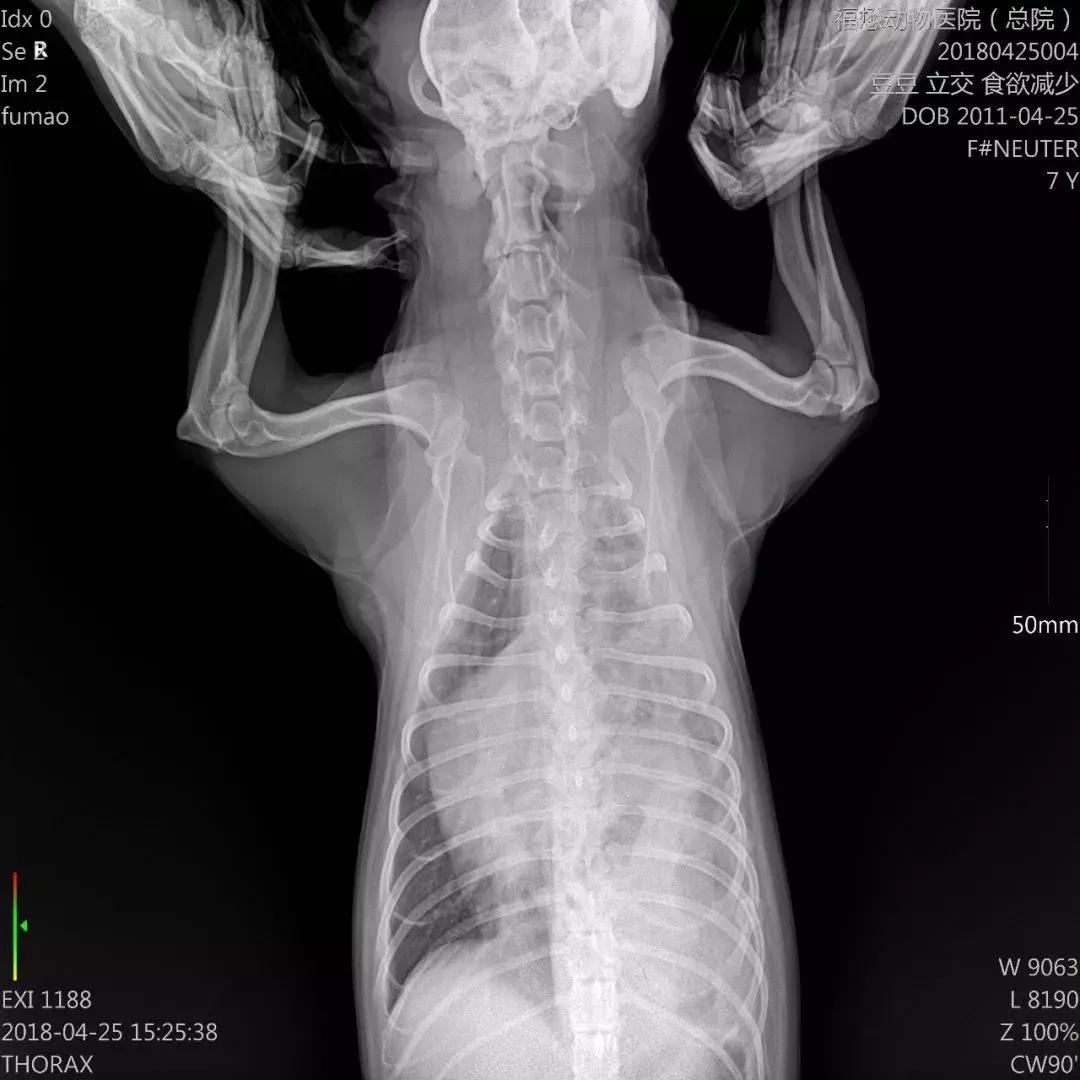

☝豆豆胸片

我们天河分院接待了豆豆,很不幸,检查过程中发现豆豆得了膈疝,腹腔的内脏器官肠道以及胃部分肝脏进入胸腔,压迫心肺,肝受损;皮肤以及黏膜黄染。